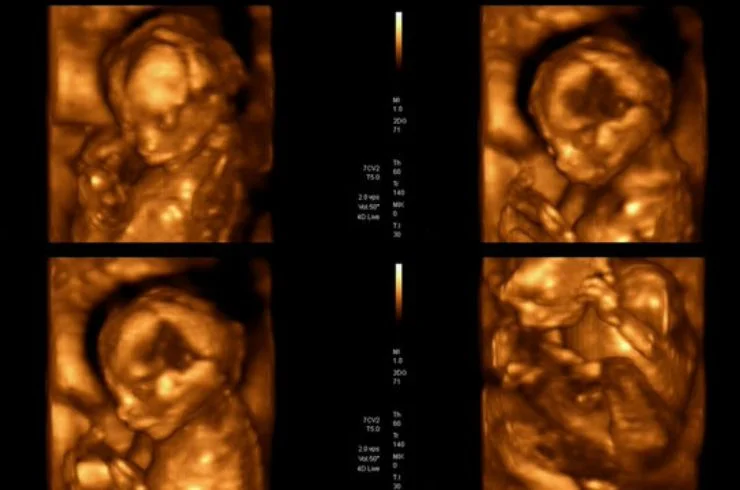

Usg Obstetrics

USG Obstetrics is an ultrasound scan used during pregnancy to monitor fetal development, check for abnormalities, assess the health of both mother and baby, and ensure proper growth.